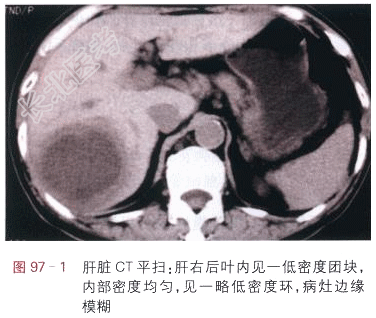

读片分析:肝右后叶包膜下见一低密度团块,呈囊性,内部密度均匀,见一略低密度囊壁,病灶边缘模糊(见图97-1),肝脏CT增强扫描:肝右后叶病灶囊壁呈环形强化,表现为“靶征”,病灶中央为低密度,周边见强化环,环周边为低密度区,病灶边缘模糊(见图97-2~图97-3)。